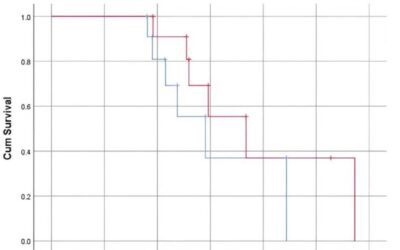

This article synthesizes the key findings, surgical techniques, and clinical insights from a lerEXPO’s 2025 Gait Keepers Journal Club regarding the use of intramedullary fibular nails for distal fibula fractures. The primary focus is on a retrospective multi-center study published in the Journal of Foot & Ankle Surgery (JFAS) in 2023, which represents the largest cohort of its kind to date.